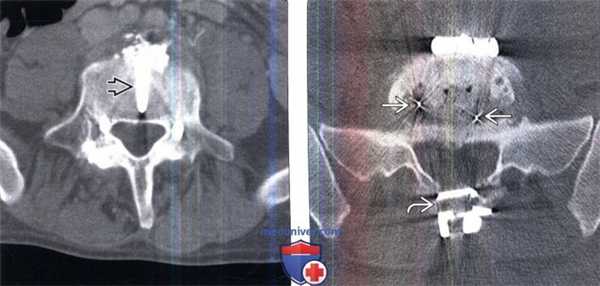

(Слева) Аксиальный КТ-срез: в теле L5 позвонка видна тень небольшого титанового винта, который выполняет роль интерферентного винта для межтелового костного трансплантата.

(Справа) Аксиальный КТ-срез: случай переднего межтелового спондилодеза с фиксацией пластиной и винтами, а также задним спондилодезом и фиксацией межостистым стабилизатором. Небольшие фокусы ослабления рентгеновского излучения представляют собой рентгенпозитивные метки на краях межтелового спейсера. Такие метки по мере интеграции костного трансплантата становятся видны все лучше.